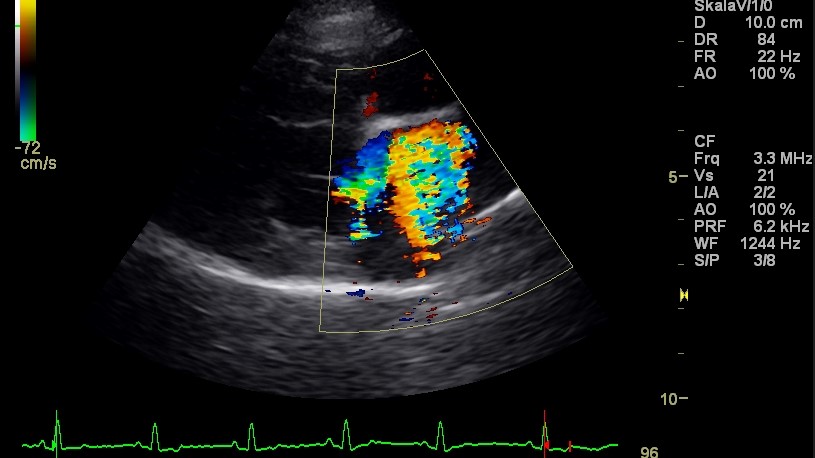

Die Untersuchung und Behandlung von Patienten mit Herzerkrankungen sind ein Spezialgebiet unserer Praxis. Zur Herzuntersuchung stehen neben dem modernen Ultraschallgerät auch EKG, Blutdruckmessung und Röntgen zur Verfügung. Erfahrung und kontinuierliche Fortbildung ermöglichen Diagnostik und Therapie auf höchstem Niveau.